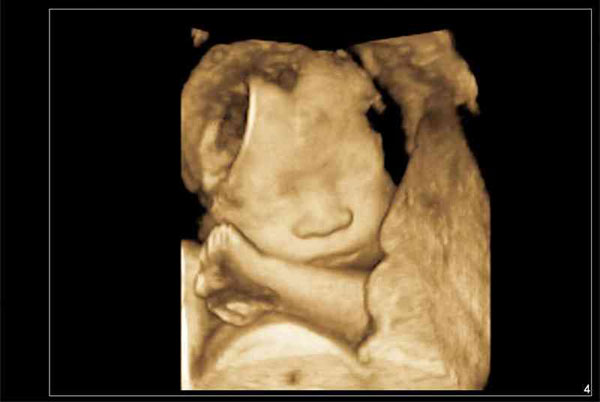

四维彩超可以完整的看得到宝宝在孕妇肚子里的形态,以及面部表情等,通常在临床上是用于给孕妇排畸比较多,也正是因为需要进行全身观察所以这个时候看宝宝性别是看的很清晰的,不过这项检查的时间会比B超更晚一些,大概是在20-24周才能进行查看。

8. 四维不是很配合:大家都知道做四维需要宝宝的积极配合,如果孩子捂住不让看,那就没法检查。女孩通常和妈妈对着脸坐着,心脏、脸部等器官没法看,因此四维彩超不太好通过。